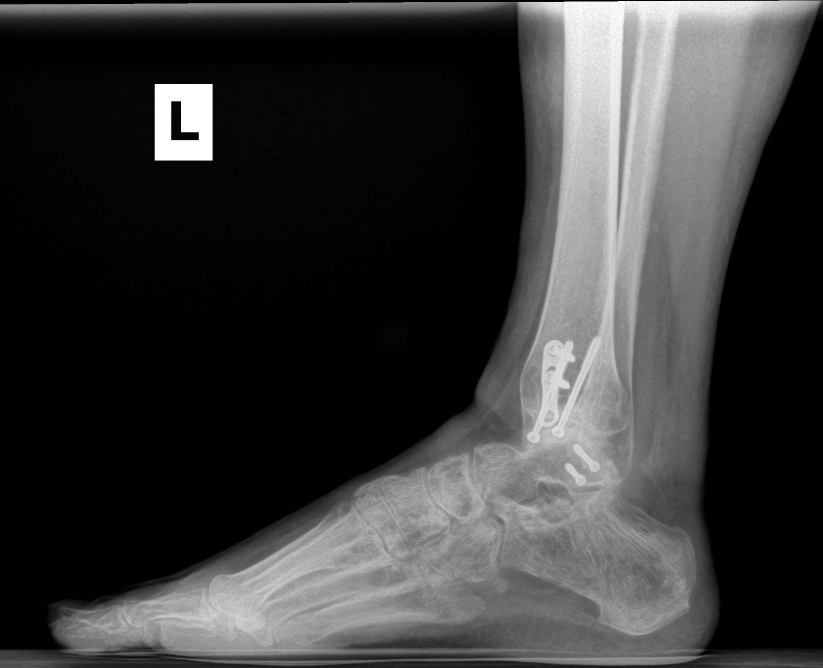

Ankle fracture repair

AF1